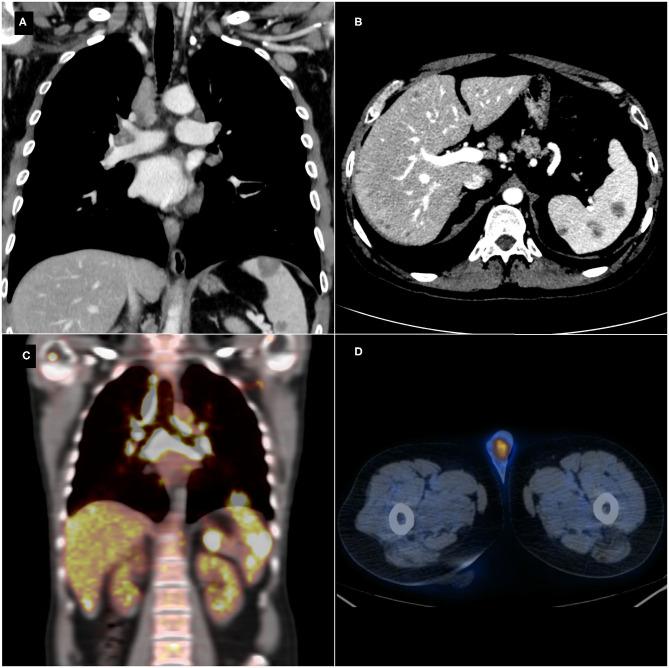

Sarcoidosis is a multisystemic disease histologically characterized by non-caseating epithelioid granulomas and multinucleated giant cells; the etiology is still uncertain, and likely related to a complex interplay between environmental and genetic factors. The genitourinary system is affected in fewer than 0.2% of all clinically diagnosed cases of sarcoidosis and in 5% of those identified in autopsy studies. In this report, we describe a case of a 42-year-old male with one hypoechoic lesion per testis on B-mode evaluation; contrast-enhanced ultrasound (CEUS) on both lesions was carried out. During the early phase, the masses showed a hypovascular appearance as compared to the surrounding testicular tissue, maintaining the hypo-enhancement in the late phase. Tissue biopsy for pathological evaluation confirmed testicular sarcoid involvement, showing non-caseating granulomas. Allowing visualization of testicular microvascularisation, CEUS may play an important role in excluding malignancy, avoiding unnecessary aggressive treatment for benign conditions, such as sarcoidosis. A review of the literature of reported cases since 2004 of sarcoidosis involving the testis is also included.

结节病是一种多系统疾病,组织学特征为非干酪样上皮样肉芽肿和多核巨细胞;其病因仍不确定,可能与环境因素和遗传因素之间的复杂相互作用有关。在所有临床诊断的结节病病例中,泌尿生殖系统受累的比例不到0.2%,而在尸检研究中发现的病例中这一比例为5%。在本报告中,我们描述了一例42岁男性,B超评估显示每个睾丸有一个低回声病变;对两个病变均进行了对比增强超声(CEUS)检查。在早期阶段,与周围睾丸组织相比,肿块表现为低血供,在晚期阶段仍保持低增强。组织活检进行病理评估证实睾丸结节病累及,显示非干酪样肉芽肿。CEUS能够显示睾丸微血管情况,在排除恶性肿瘤、避免对结节病等良性疾病进行不必要的积极治疗方面可能发挥重要作用。本文还对2004年以来报道的累及睾丸的结节病病例文献进行了综述。